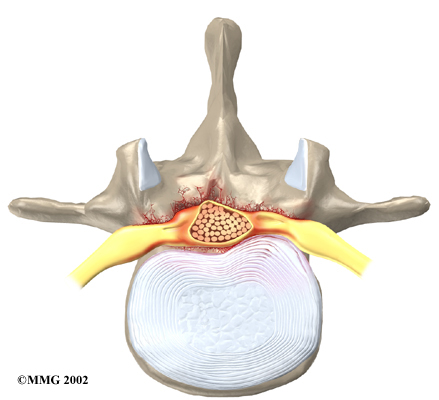

Disc herniation: Spinal stenosis can occur when an intervertebral disc in the low back (ruptures). Normally, the shock-absorbing disc is able to handle the downward pressure of gravity and the strain from daily activities. However, if the pressure on the disc is too strong, such as landing from a fall in a sitting position, the nucleus inside the disc may rupture through the outer annulus and squeeze out of the disc. This is called a disc herniation. If an intervertebral disc herniates straight backward, it can press against the nerves in the spinal canal, causing symptoms of spinal stenosis.